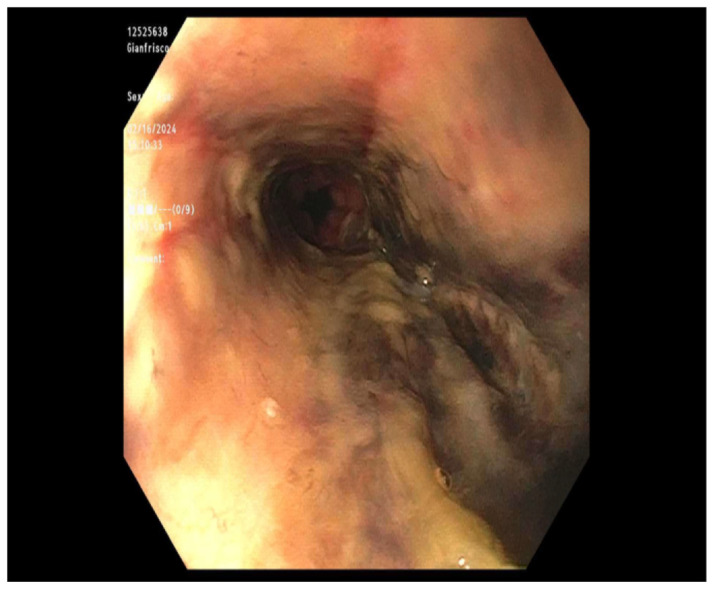

Acute esophageal necrosis (AEN) is a rare syndrome, characterized by extensive circumferential necrosis of the esophageal mucosa at the gastroesophageal junction. AEN carries significant morbidity and mortality, and early recognition is crucial for management. We present a case series of AEN in two critically ill patients, one who presented with coffee ground emesis and diabetic ketoacidosis (DKA) and the other one who presented with upper gastrointestinal bleed in the setting of malignancy and concurrent infection with active antibiotic use. Prompt diagnosis and management of both AEN and its underlying causes are crucial to improve patient outcomes.